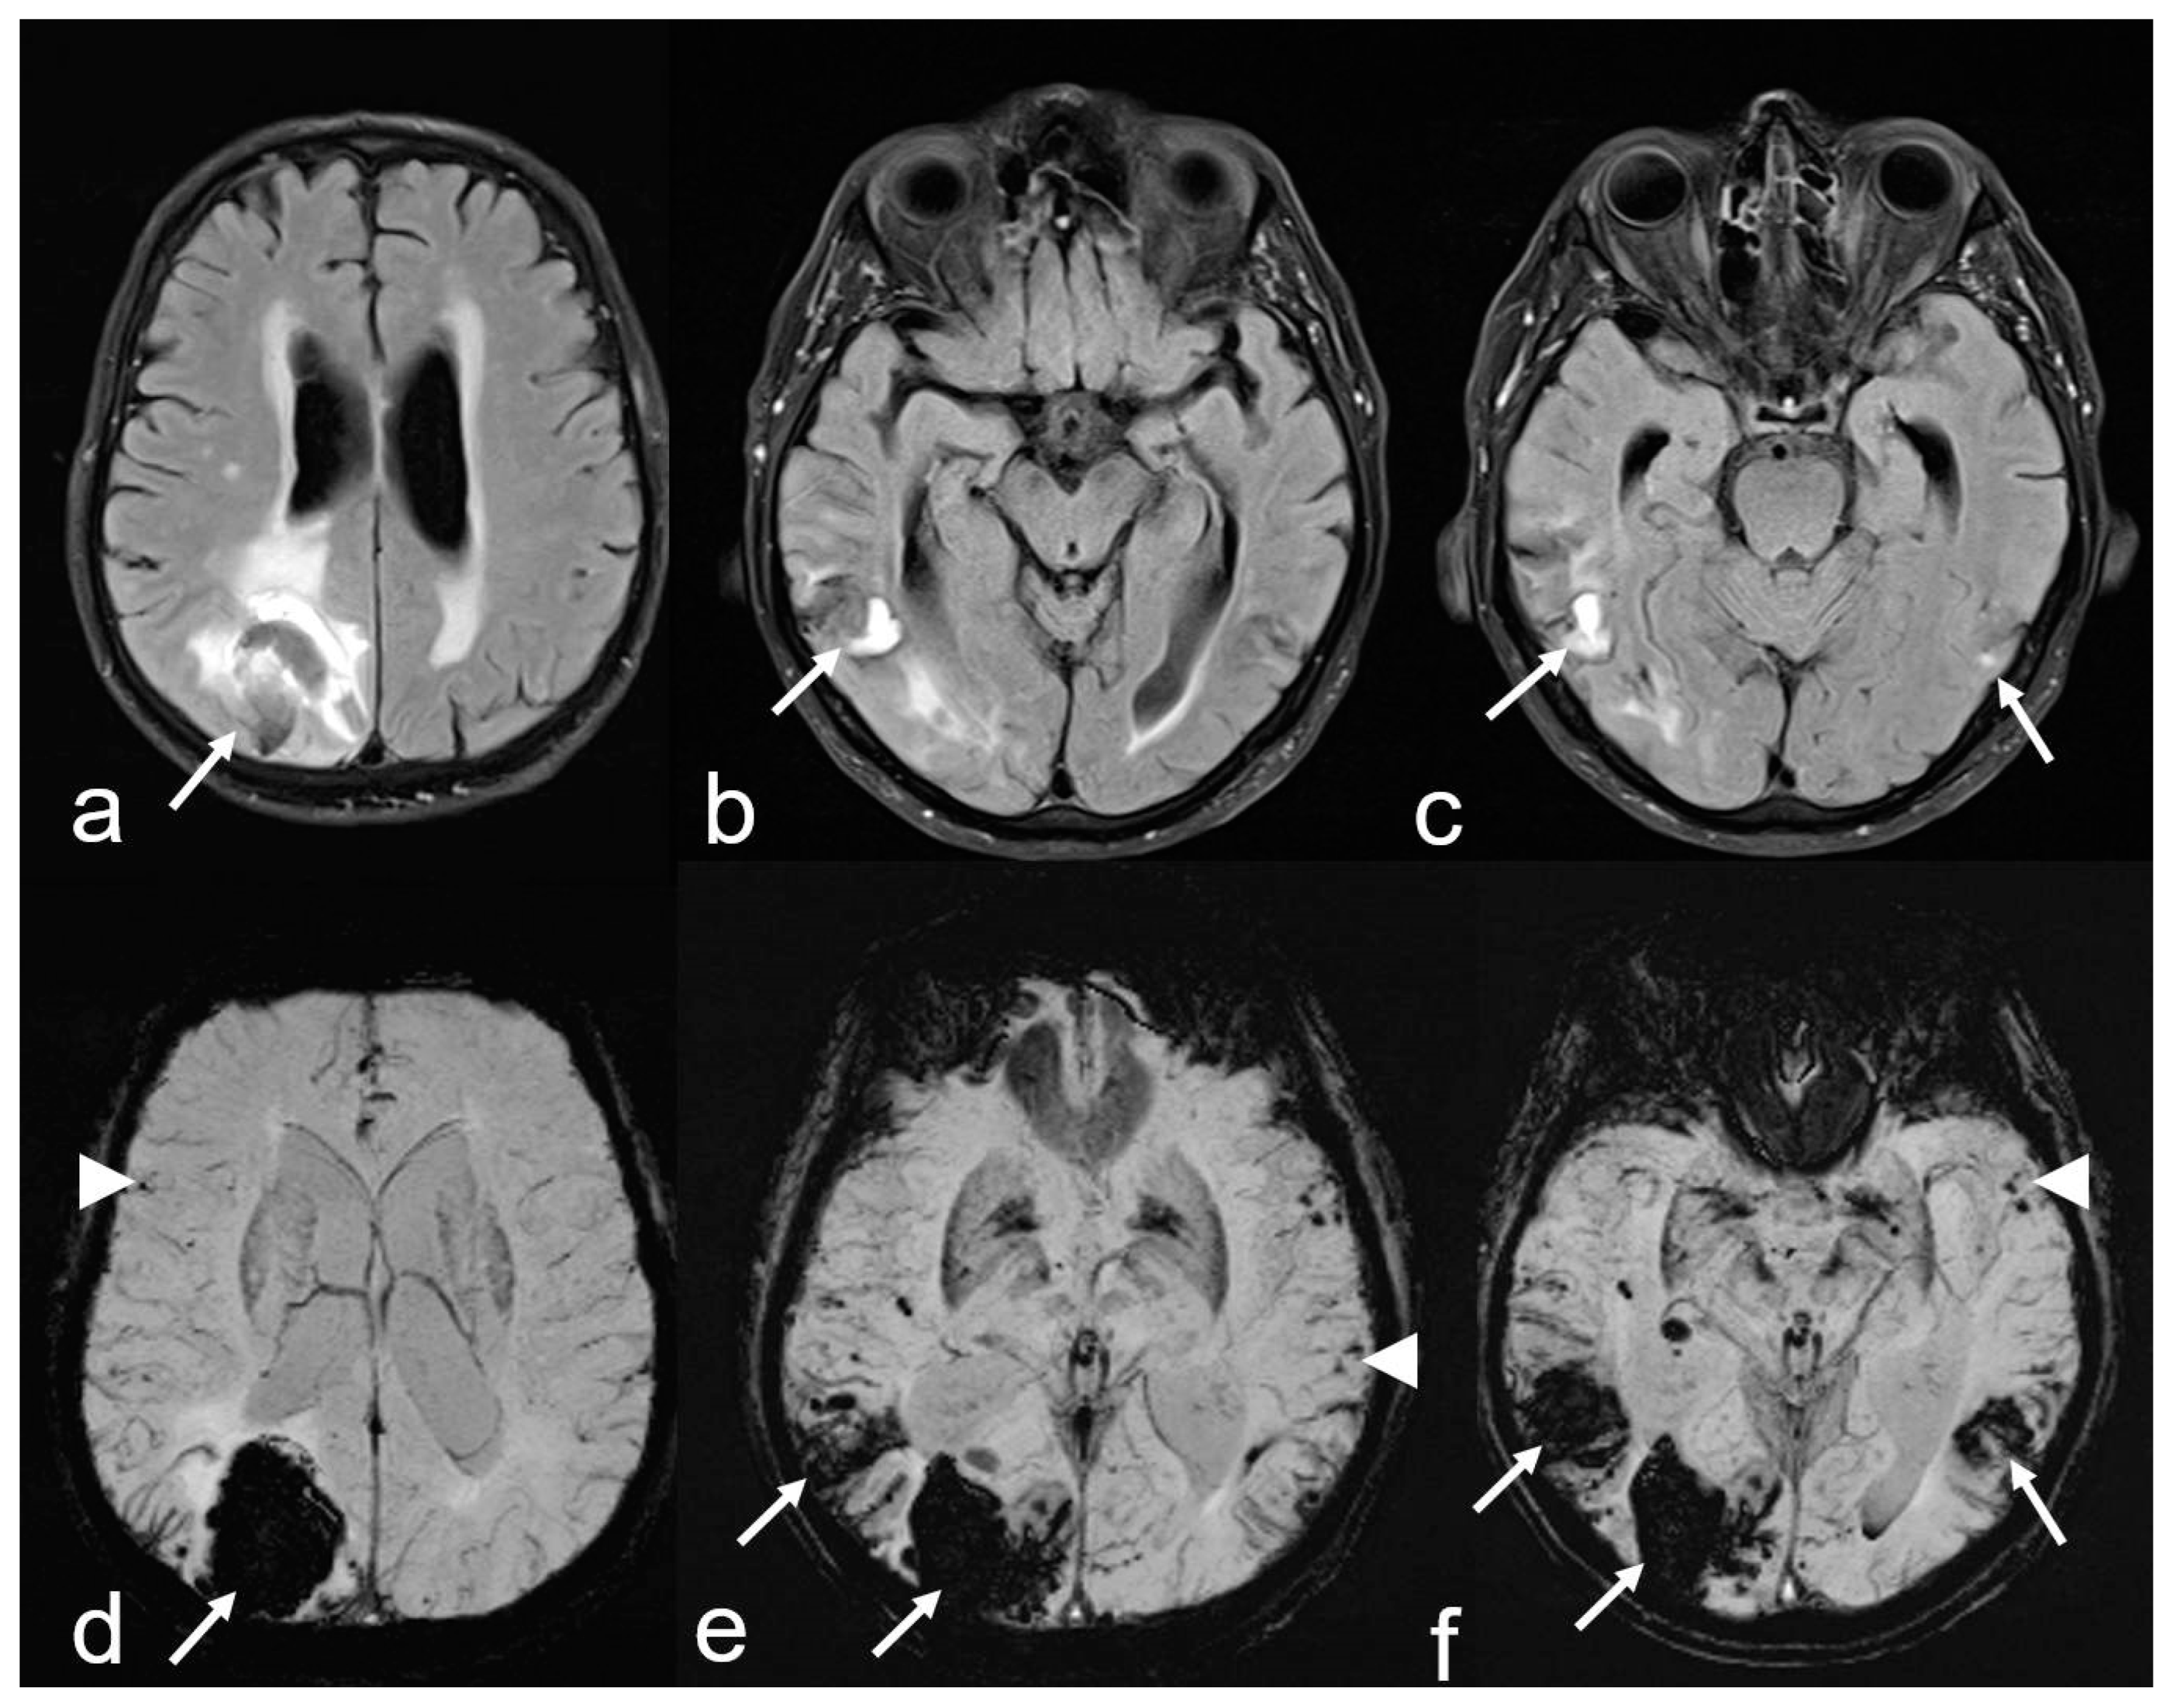

Figure 2.

Recurrent intracerebral hemorrhages (ICH) within 2 years in a 74-year-old man with a history of progressive cognitive impairment. The patient was on antihypertensive medication and a statin but had neither antithrombotic drugs nor anticoagulant therapy. The final diagnosis was new lobar ICB due to probable CAA in accordance with the 2.0 version of the Boston criteria [38]. Axial FLAIR (fluid attenuated inversion recovery) images (a–c) showing three ICHs at different time points parieto-occipital right ((a,d): arrow), temporal right ((b–e): arrow) and temporal left ((c,f): arrow); (d–f): susceptibility-weighted imaging (SWI; arrow) disclosing additional multiple microbleeds (MB) with temporal accentuation (d–f: arrowhead); MRI 1.5 T Siemens AREA.

2. Cortical and subcortical microbleeds (MB), which have been identified as a risk factor for lobar ICH and ischemia, have also been associated with cognitive impairment [38,53,54,55]. In contrast to hypertensive microangiopathy caused by lipohyalinosis, which typically affects the basal ganglia, thalamus, pons and cerebellum [55,56,57,58,59,60], MB are generally absent in these regions in CAA [38,54,61]. Due to the neurodegenerative and cerebrovascular processes associated with Aß deposits, MBs are preferentially localized in the parieto-occipital regions in both CAA and AD (Figure 1, Figure 2 and Figure 3) [3,19,53,54,61].